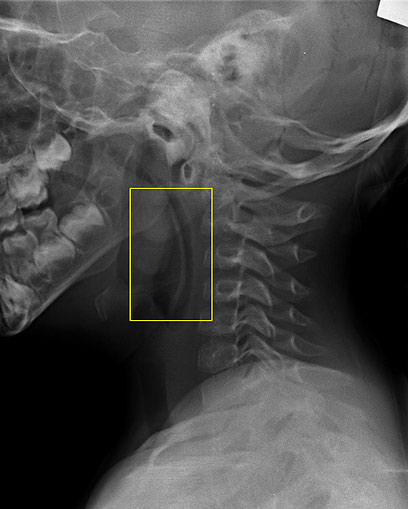

הכפית התקועה בגרונו של הפעוט. הוצאה בניתוח (באדיבות בי"ח העמק)

בחדר המיון קיבל את אהוד ד"ר דרור אשכנזי, מומחה בכיר לאף אוזן וגרון, שקבע כי יש לנתח אותו בדחיפות. "היה לי ברור כי ראש הכפית תקוע באזור הלוע העליון של אהוד, ואכן צילום הרנטגן אישש את חשדותיי. כמובן שמדובר במצב מסכן חיים", סיפר ד"ר אשכנזי.